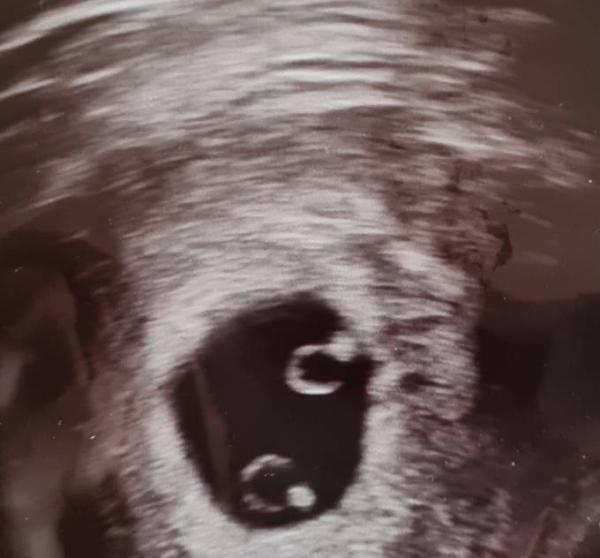

Danke ihr Lieben!! Es sieht alles gut aus! Das Herz hat ordentlich geschlagen So ein schöner Moment Er hat mich 2 Tage zurĂŒck datiert, auf 6+4. Aber das ist ja nicht wirklich viel und kann nĂ€chste Woche ganz anders aussehen. Sagt er zumindest Ich darf am 3.12. wieder hin.. Wenn die nĂ€chsten 3 Wochen vorbei sind, kann ich hoffentlich aufatmen Aber die erste HĂŒrde ist geschafft Dieses Mal wird es bei uns allen gut

GlĂŒckwunsch wie bei mir Ă€hnlich, mein KrĂŒmel ist auch sehr mini aber Hauptsache das Herzchen schlĂ€gt

GlĂŒckwunsch !!! Ich habe am 16ten meinen ersten Termin beim Frauenarzt gehabt (6+2) da hatte mir die FrauenĂ€rztin gesagt ich soll mir keine Hoffnungen machen sie kann eine intakte Schwangerschaft nicht bestĂ€tigen. Unwohl hatte ich mich definitiv gefĂŒhlt Bin eine Woche drauf am 23ten zur meiner alte FrauenĂ€rztin gegangen (40km fahrt) und was siehe da 2 krĂ€ftige herzschlĂ€ge nach 3 Jahren hat es nun endlich geklappt mit doppeltem GlĂŒck (Haben schon eine 5 jĂ€hrige tochter)

Bild zu